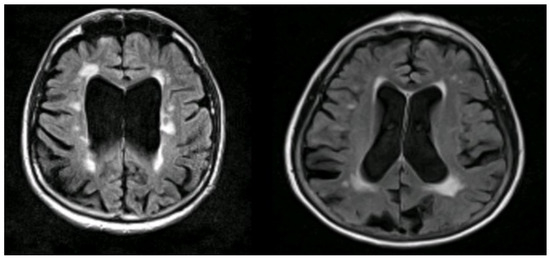

Figure 2.

An example of FDG-PET imaging in a participant from an Alzheimer’s disease clinical trial who met research criteria for probable AD, showing temporo-parietal hypo-metabolism(violet diagonal band) and normal areas of metabolism(golden). T is the thickness (2.2 mm) and P is the position relative to the isocentre of the field of view(FoV).(Courtesy—Alison D. Murray, University of Aberdeen).